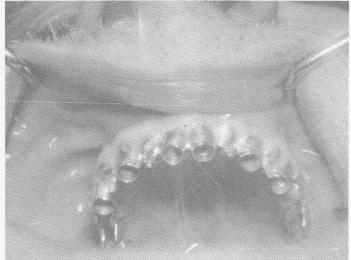

Fig. 10-255. The template was fitted over the edentulous

1 Template fitted over maxillary edentulous arch